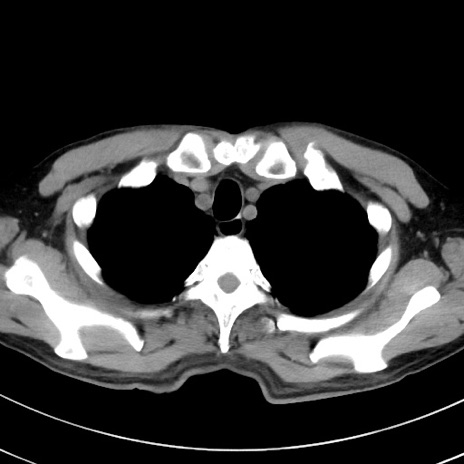

症例38(横断像)

【症例】70歳代 男性

【主訴】腹痛・嘔吐

【現病歴】昨晩より、嘔吐・腹痛あり。今朝になっても嘔吐あり。来院。

【既往歴】心臓バイパス手術、開腹胆摘、腸閉塞

【身体所見】BP 107/71mmHg、HR 116/min、腹部:平坦、軟、下腹部に軽度圧痛あり。反跳痛なし。

【データ】WBC 15100、CRP 0.32